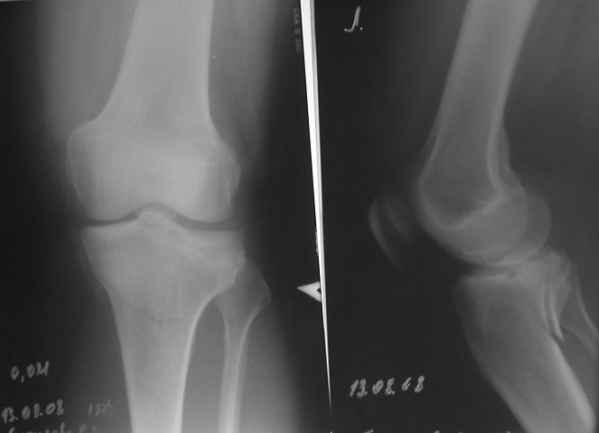

конечно есть, просто не дошли. Посылаю

Действительно, доступ капризный. Из имплантов я бы выбрал Tomofix от синтез.

Проблема тут, видимо, не в выборе имплантата, а в том, что надо делать остеосинтез задним доступом. А пластинка подойдет практически любая - небольшая T-образная, хоть две 1/3 трубчатых. Угловая стабильность необязательна. Лишь бы трансплантат не вываливался. На КТ хорошо бы увидеть еще и срезы в сагиттальной и фронтальной плоскостях.